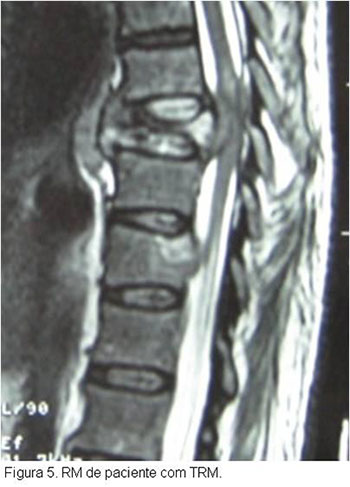

O tratamento do doente vítima de TRM inicia-se na abordagem inicial do paciente politraumatizado, segundo especificações do ATLS , tomando- se os cuidados necessários quanto a imobilização da coluna a fim de se evitar a progressão ou mesmo o surgimento de lesões neurológicas. Após a estabilização do paciente e realização diagnóstica de TRM com exame físico e exames secundários de imagem como Rx, TC ou RM cervical, deve-se proceder a estabilização da lesão cervical, geralmente com o uso de tração em halo craniano, até a programação do tratamento definitivo, que geralmente consiste na redução cruenta da fratura e fixação interna da mesma.Caso o paciente tenha sido atendido nas primeias 8 horas após o trauma deverá ser instituído a corticoterapia, salvo os pacientes com contra-indicações, segundo protocolo instituído pelo NASCISIII, a fim de evitar possíveis lesões secundárias à medula.Este protocolo consiste na aplicação de metilpredinisolona na dose de 30mg/kg ev na primeira hora, seguido de 5,4mg/kg/hora nas próximas 23hs, isto quando paciente chega ao hospital dentro de 3hs do trauma. Quando chega entre 3-8hs, manter esquema de 5,4mg/kg/hora por 48hs. Após 8hs não realizar corticoterapia. Contra-indicações para corticoterapia: gravidez, criança, imunossuprimido, fx exposta, infeccção grave ou risco de vida.Cuidados: monitorar PA, glicemia, e realizar proteção gástrica.

O tratamento cirúrgico tem se beneficiado muito das inovações tecnológicas que propõem cada vez mais técnicas mais rápidas, seguras e com maior poder de estabilização da lesão óssea.O tratamento farmacológico restringe-se a corticoterapia a fim de evitar lesões secundárias, porém novas drogas estão sendo testadas e poderão ser introduzidas num futuro próximo, como o gangliosídeo.O tratamento biológico consiste na maior esperança para o lesado medular, a expectativa de que o uso de células tronco possa proporcionar uma restauração da via neurológica acometida no trauma, vem estimulando diversas pesquisas nesta direção, entretanto ainda estamos em fase inicial desta metodologia.Já a terapia por meios físicos, como a câmara hiperbárica, não demonstrou benefícios nos ensaios animais (figuras 2, 3, 4, 5, 6, 7).